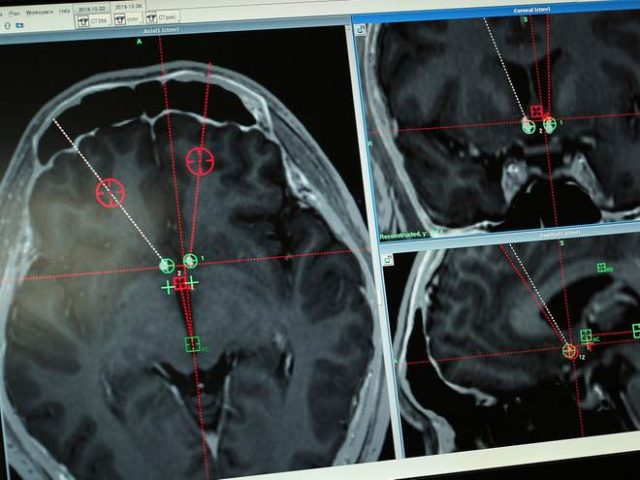

Penanaman Implan Otak Untuk Atasi Kecanduan Narkoba

Dalam upayanya mengatasi kecanduannya bertahun-tahun terhadap metamfetamin, seorang pria di Cina merelakan otaknya dibor untuk ditanami semacam implan elektroda - yang dinamakan DBS, dalam sebuah percobaan pertama secara klinis terhadap alat tersebut, The Independent melaporkan. Tingkat keberhasilannya terbukti setelah prosedur pembedahan di Rumah Sakit Ruijin Shanghai, ia masih tetap terbebas dari ketergantungannya terhadap narkoba selama lebih dari enam bulan. "Untuk berbagai...